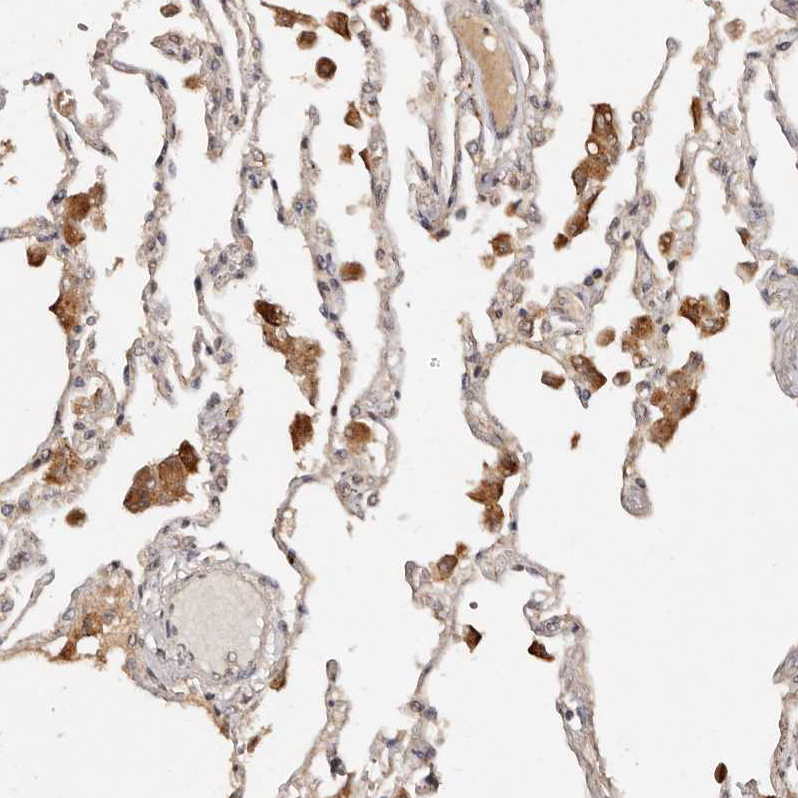

Immunohistochemical staining of human lung shows moderate cytoplasmic positivity in macrophages.